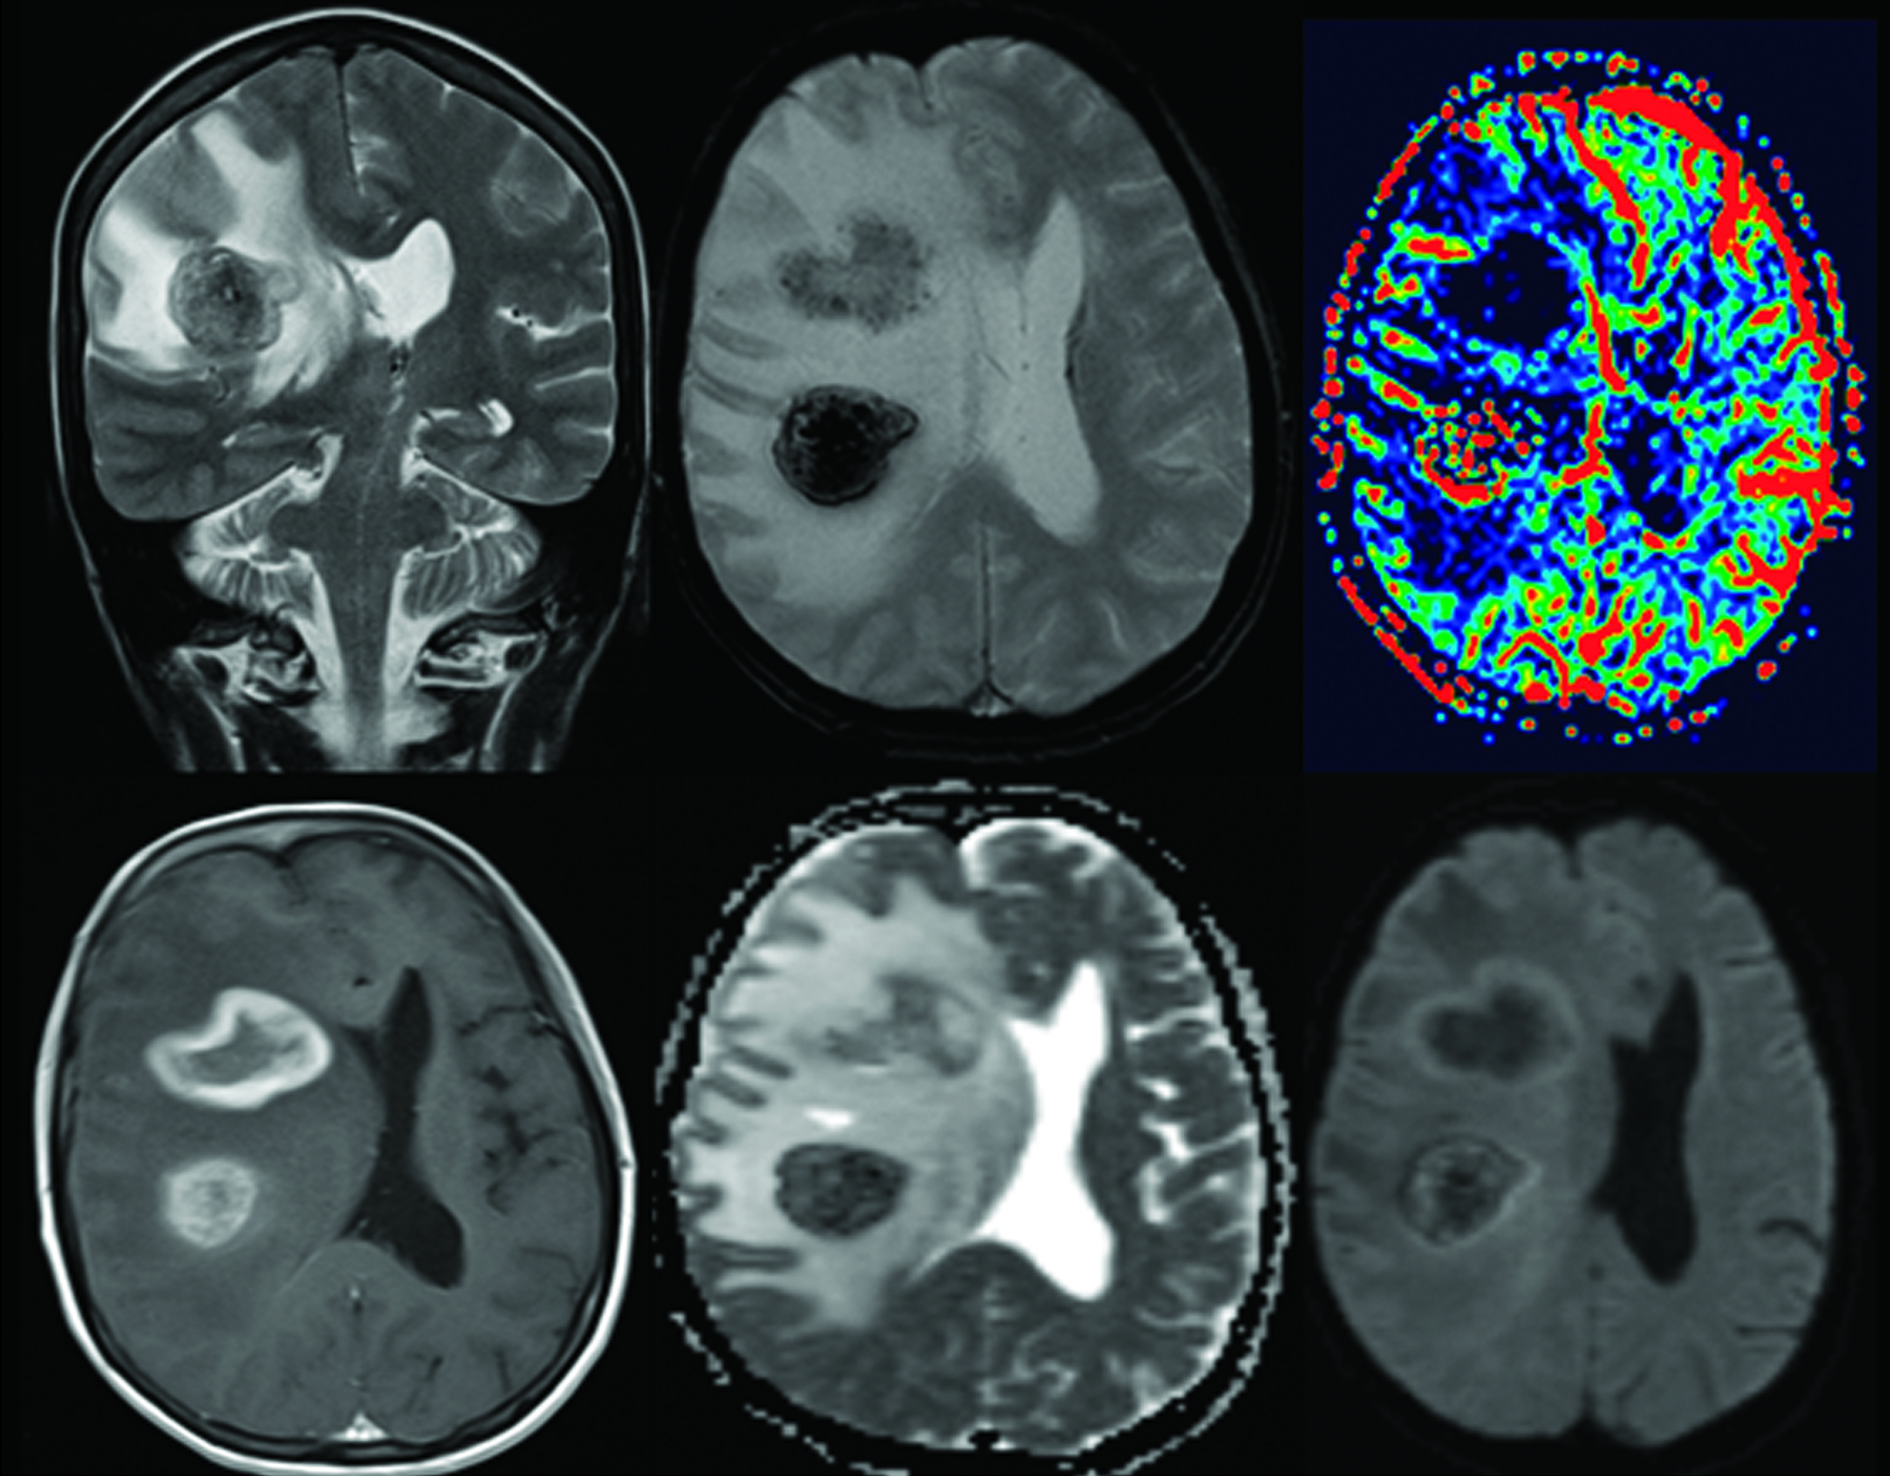

Se realiza TC de cráneo (Fig. 1), donde se constata la presencia de dos lesiones intra-axiales frontales derechas, con sectores espontáneamente hiperdensos en relación a sangrado. Ambas presentan realce en anillo grueso e irregular con el medio de contraste. En RM son de intensidad de señal heterogénea, hipointensas en T2/FLAIR (del inglés “fluid attenuated inversión recovery”), hiperintensas en T1, con realce periférico grueso, continuo e irregular con gadolinio. En secuencias eco de gradientes (GRE) se observan zonas de artificio de susceptibilidad magnética en relación a áreas de sangrado interno. En difusión-ADC (coeficiente de difusión aparente) se objetivan áreas periféricas de restricción y en el estudio de perfusión disminución del volumen sanguíneo cerebral (Fig. 2). Se completó estudio con TC de cuello, tórax, abdomen y pelvis, sin identificarse lesiones sugerentes de compromiso nodal, hepático o esplénico.

Figura 2

a) Corte coronal secuenciada ponderada en T2.

b) Corte axial secuencia GRE.

c) Perfusión, mapa de volumen sanguíneo cerebral.

d) Corte axial ponderada en T1 tras la administración de Gadolinio.

e) Difusión.

f) Mapa de ADC. Las lesiones presentan intensidad de señal heterogénea, hipointensas en T2/FLAIR, hiperintensas en T1, con realce periférico grueso, continuo e irregular con el gadolinio. Asocian restricción en difusión también periférica, concordante con las áreas de realce. En secuencias GRE presentaban sectores de artificio de susceptibilidad magnética, en relación a sangrado. La lesión frontal anterior muestra disminución del volumen sanguíneo cerebral (VSC) en el estudio de perfusión. La lesión posterior presenta importantes áreas de hemorragia que generan artefactos y dificultan la correcta interpretación del estudio de perfusión. Se observa además, importante edema perilesional y efecto de masa locorregional.

En función del severo inmunocompromiso de la paciente, asociado a la presencia de lesiones múltiples con realce en anillo, se planteó desde el punto de vista imagenológico, que las lesiones fueran en primera instancia de etiología infecciosa. La toxoplasmosis es la infección oportunista más frecuente y la causa más frecuente de masa intracraneal en el paciente SIDA (4). La áreas de hemorragia interna extensas que presentaron ambas lesiones, favoreció el diagnóstico de toxoplasmosis frente a los diagnósticos diferenciales, principalmente el LPSNC, dado que en este último la hemorragia es excepcional (3). La restricción moderada en difusión-ADC y el bajo volumen sanguíneo cerebral orientaron a dicha etiología. Dado lo voluminoso de las lesiones y su bajo número de presentación, se incluyó el LPSNC entre los planteos diferenciales más probables.